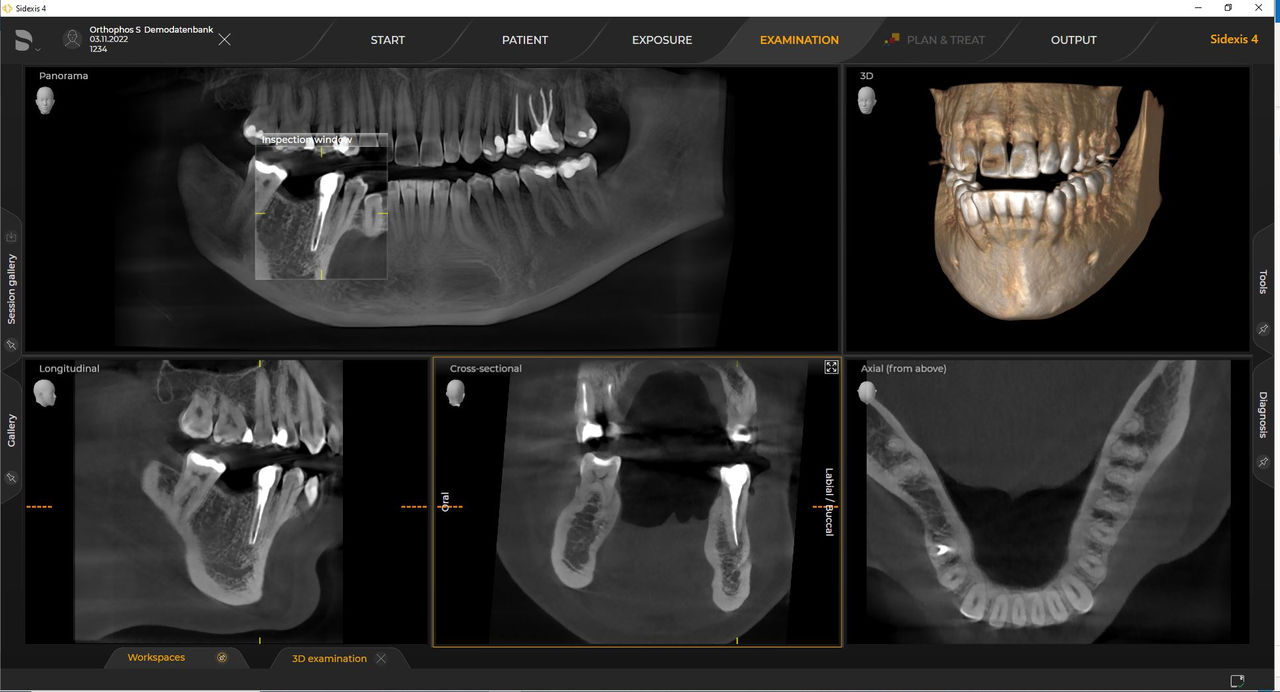

Dentsply Sirona-röntgeneenheden werken uitsluitend met Sidexis 4. Toch is de gegevensmigratie van Sidexis XG naar Sidexis 4 heel eenvoudig. Sidexis 4 zorgt voor een volledige digitale ervaring met de nieuwste tools

Orthophos S 2D maakt een 3D-upgrade mogelijk. Axeos is een speciale hybride unit. De Orthophos E heeft deze optie niet.